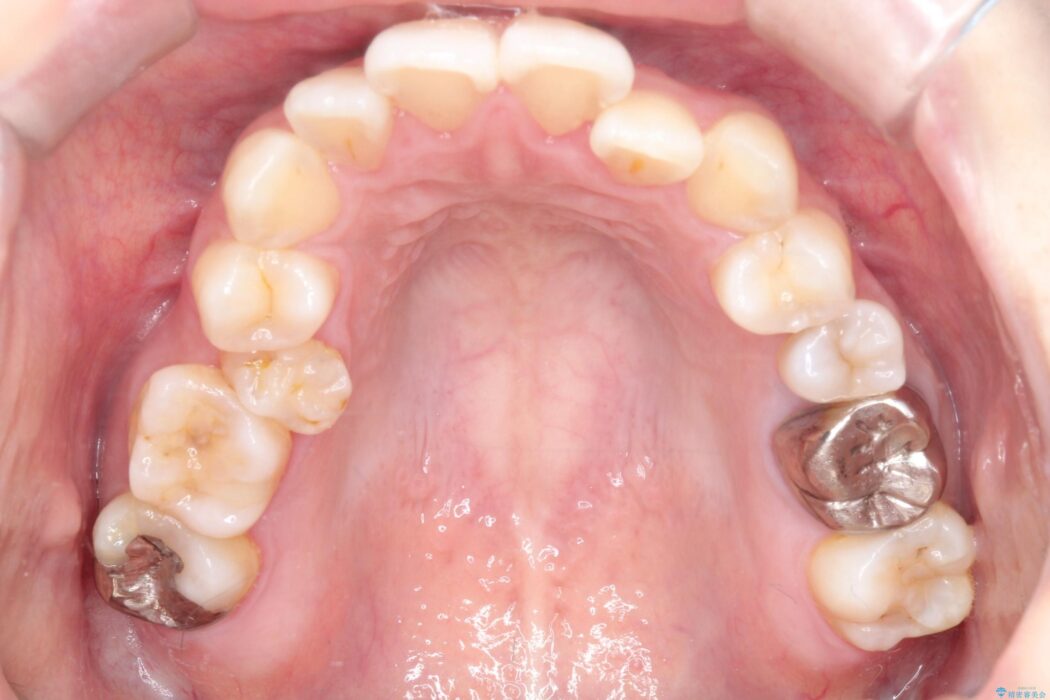

口元を下げて前突感を無くしたい、下の歯の凹凸も無くしたいとご来院された患者様です。

アゴの骨格的なズレがあったため、歯の真ん中を完全に合わせることは不可能と説明。上下4本抜歯を行い、ワイヤー矯正で噛み合わせの大きな改善を目指しました。

口元の突出感が改善され、大変ご満足いただけました。